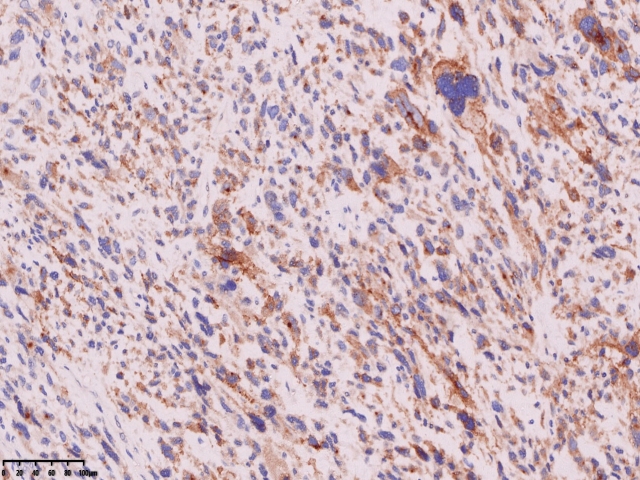

免疫组化

SMA

Caldesm部分+

CD10部分+

CD10

ki67

cd34

ER 部分+

PR-

Desmin-

会诊结果:子宫体间叶组织来源的肿瘤,形态学符合恶性。依据免疫组化结果,可排除肌源性肿瘤、胃肠间质瘤、子宫内膜间质肿 瘤、神经源性肿瘤、孤立性纤维性肿瘤等。 考虑可能为纤维肉瘤。